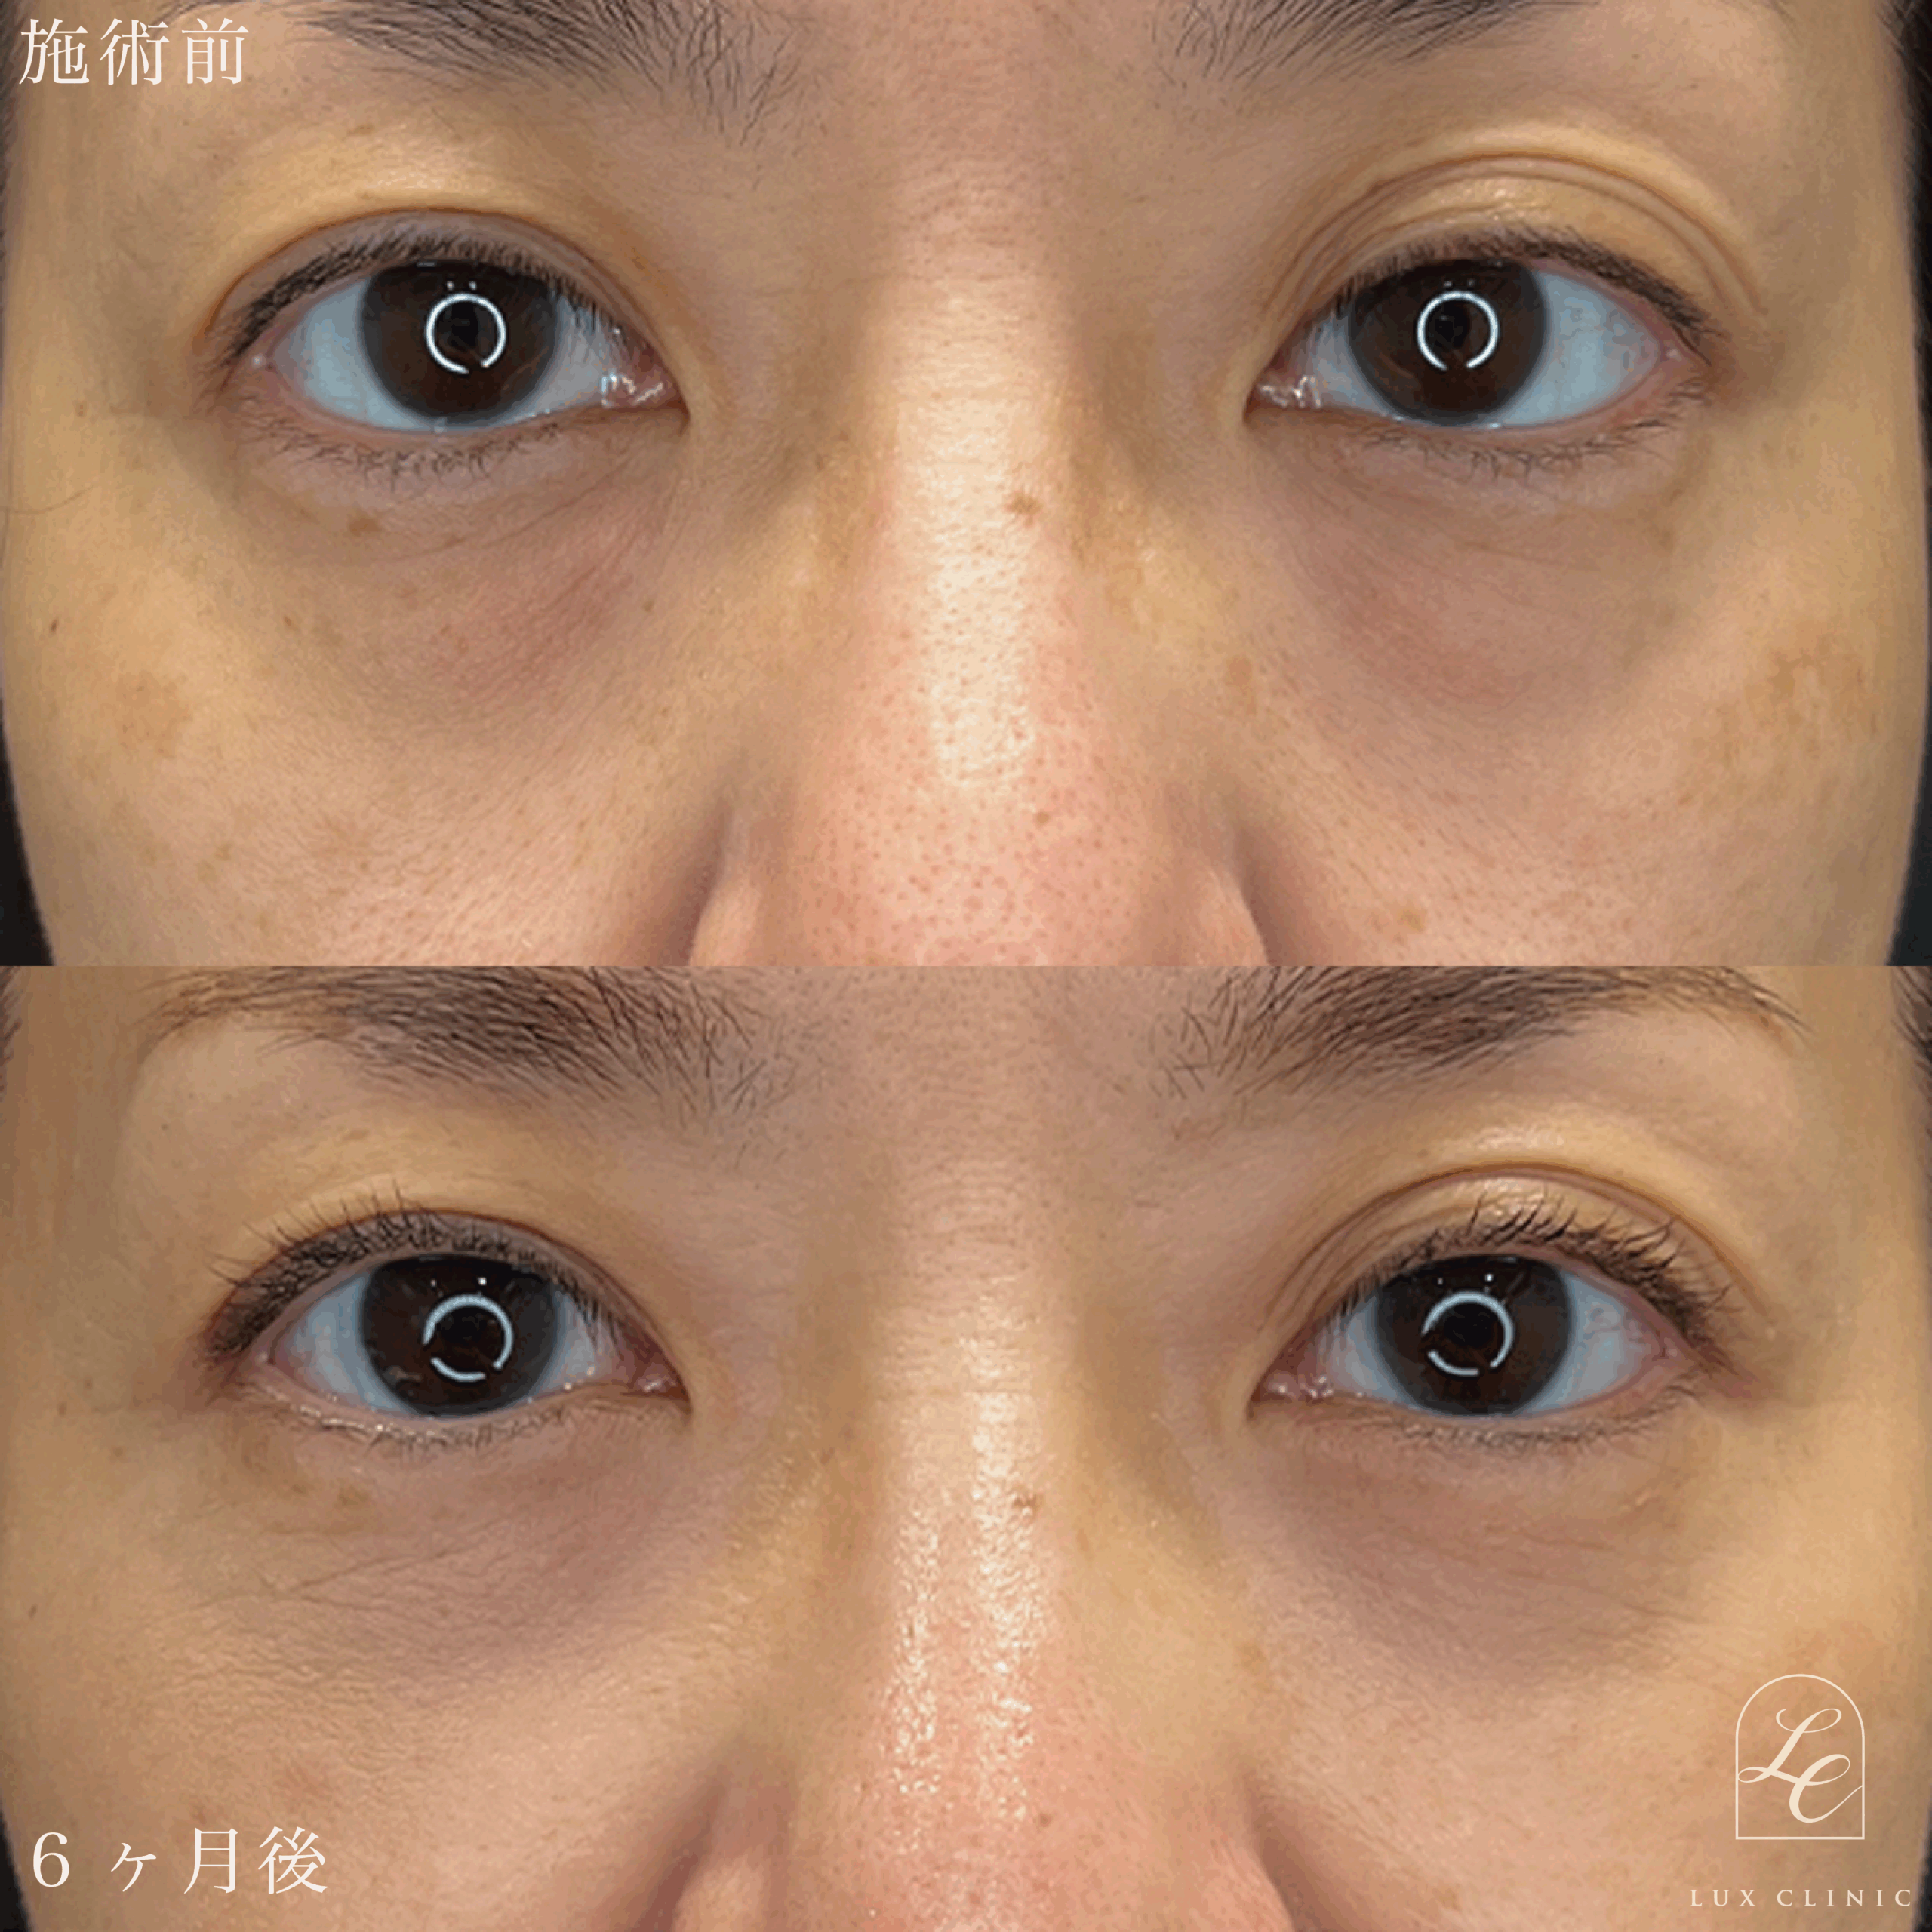

Case症例写真

裏ハムラ法